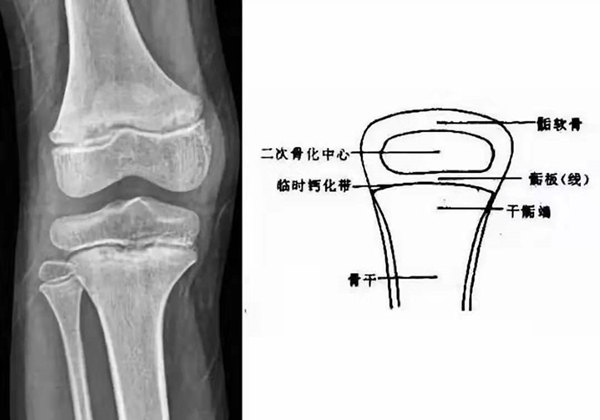

我們都知道,人體的高矮是由骨骼的生長發(fā)育決定的,特別是下肢長骨。長骨呈長管狀,在長骨的兩端有一種專管骨骼生長的骺軟骨,它與干骺端之間有一盤狀軟骨結(jié)構(gòu)稱為骺板(線),在幼兒的X光片上表現(xiàn)為一條較寬的透光帶。 (見下圖)

未成年時(shí)隨著年齡的增加骺軟骨端不斷骨化,骨骼就不斷增長。當(dāng)骨骺線完全閉合時(shí)骨骼就停止生長,個子也就不再增長了。一般骨骺端完全閉合的年齡是18~20歲左右。